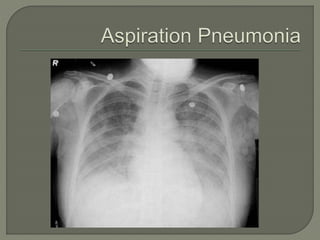

Aspiration

• Gastric vs Transpyloric Feeding

 Significant reduction if tube is past the Ligament of

Trietz